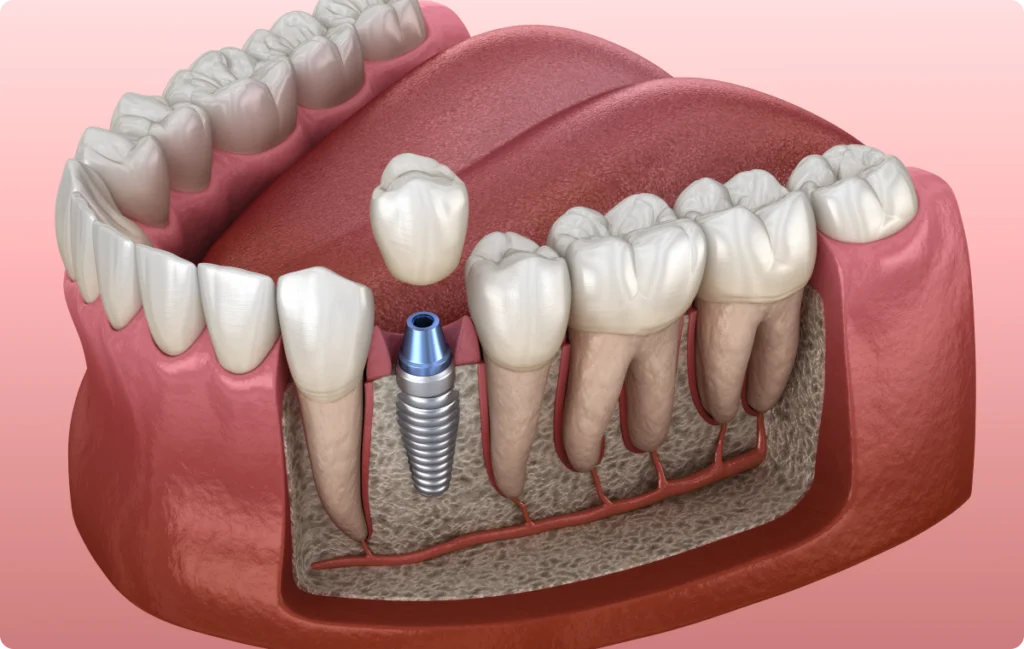

Un implant dentaire agit comme une racine artificielle ancrée dans l’os. S’il ne souffre pas de carie, il reste exposé à d’autres risques : notamment les infections gingivales ou osseuses appelées péri-implantites.

Ces inflammations, souvent liées à une accumulation de plaque dentaire, peuvent entraîner une perte osseuse progressive autour de l’implant. Dans les cas les plus avancés, elles compromettent sa stabilité.

L’os qui entoure l’implant joue un rôle essentiel : il en assure la stabilité. Or, cet os peut se résorber en cas de déséquilibre mécanique ou d’inflammation chronique.

Les radiographies de suivi permettent de comparer l’évolution osseuse et de détecter toute perte précoce.